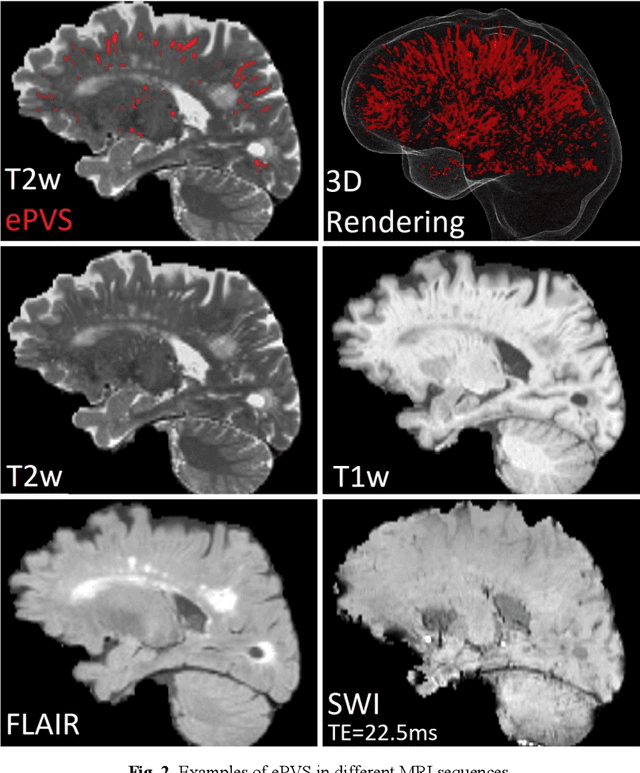

Abstract:Deep learning has been demonstrated effective in many neuroimaging applications. However, in many scenarios the number of imaging sequences capturing information related to small vessel disease lesions is insufficient to support data-driven techniques. Additionally, cohort-based studies may not always have the optimal or essential imaging sequences for accurate lesion detection. Therefore, it is necessary to determine which of these imaging sequences are essential for accurate detection. In this study we aimed to find the optimal combination of magnetic resonance imaging (MRI) sequences for deep learning-based detection of enlarged perivascular spaces (ePVS). To this end, we implemented an effective light-weight U-Net adapted for ePVS detection and comprehensively investigated different combinations of information from susceptibility weighted imaging (SWI), fluid-attenuated inversion recovery (FLAIR), T1-weighted (T1w) and T2-weighted (T2w) MRI sequences. We conclude that T2w MRI is the most important for accurate ePVS detection, and the incorporation of SWI, FLAIR and T1w MRI in the deep neural network could make insignificant improvements in accuracy.